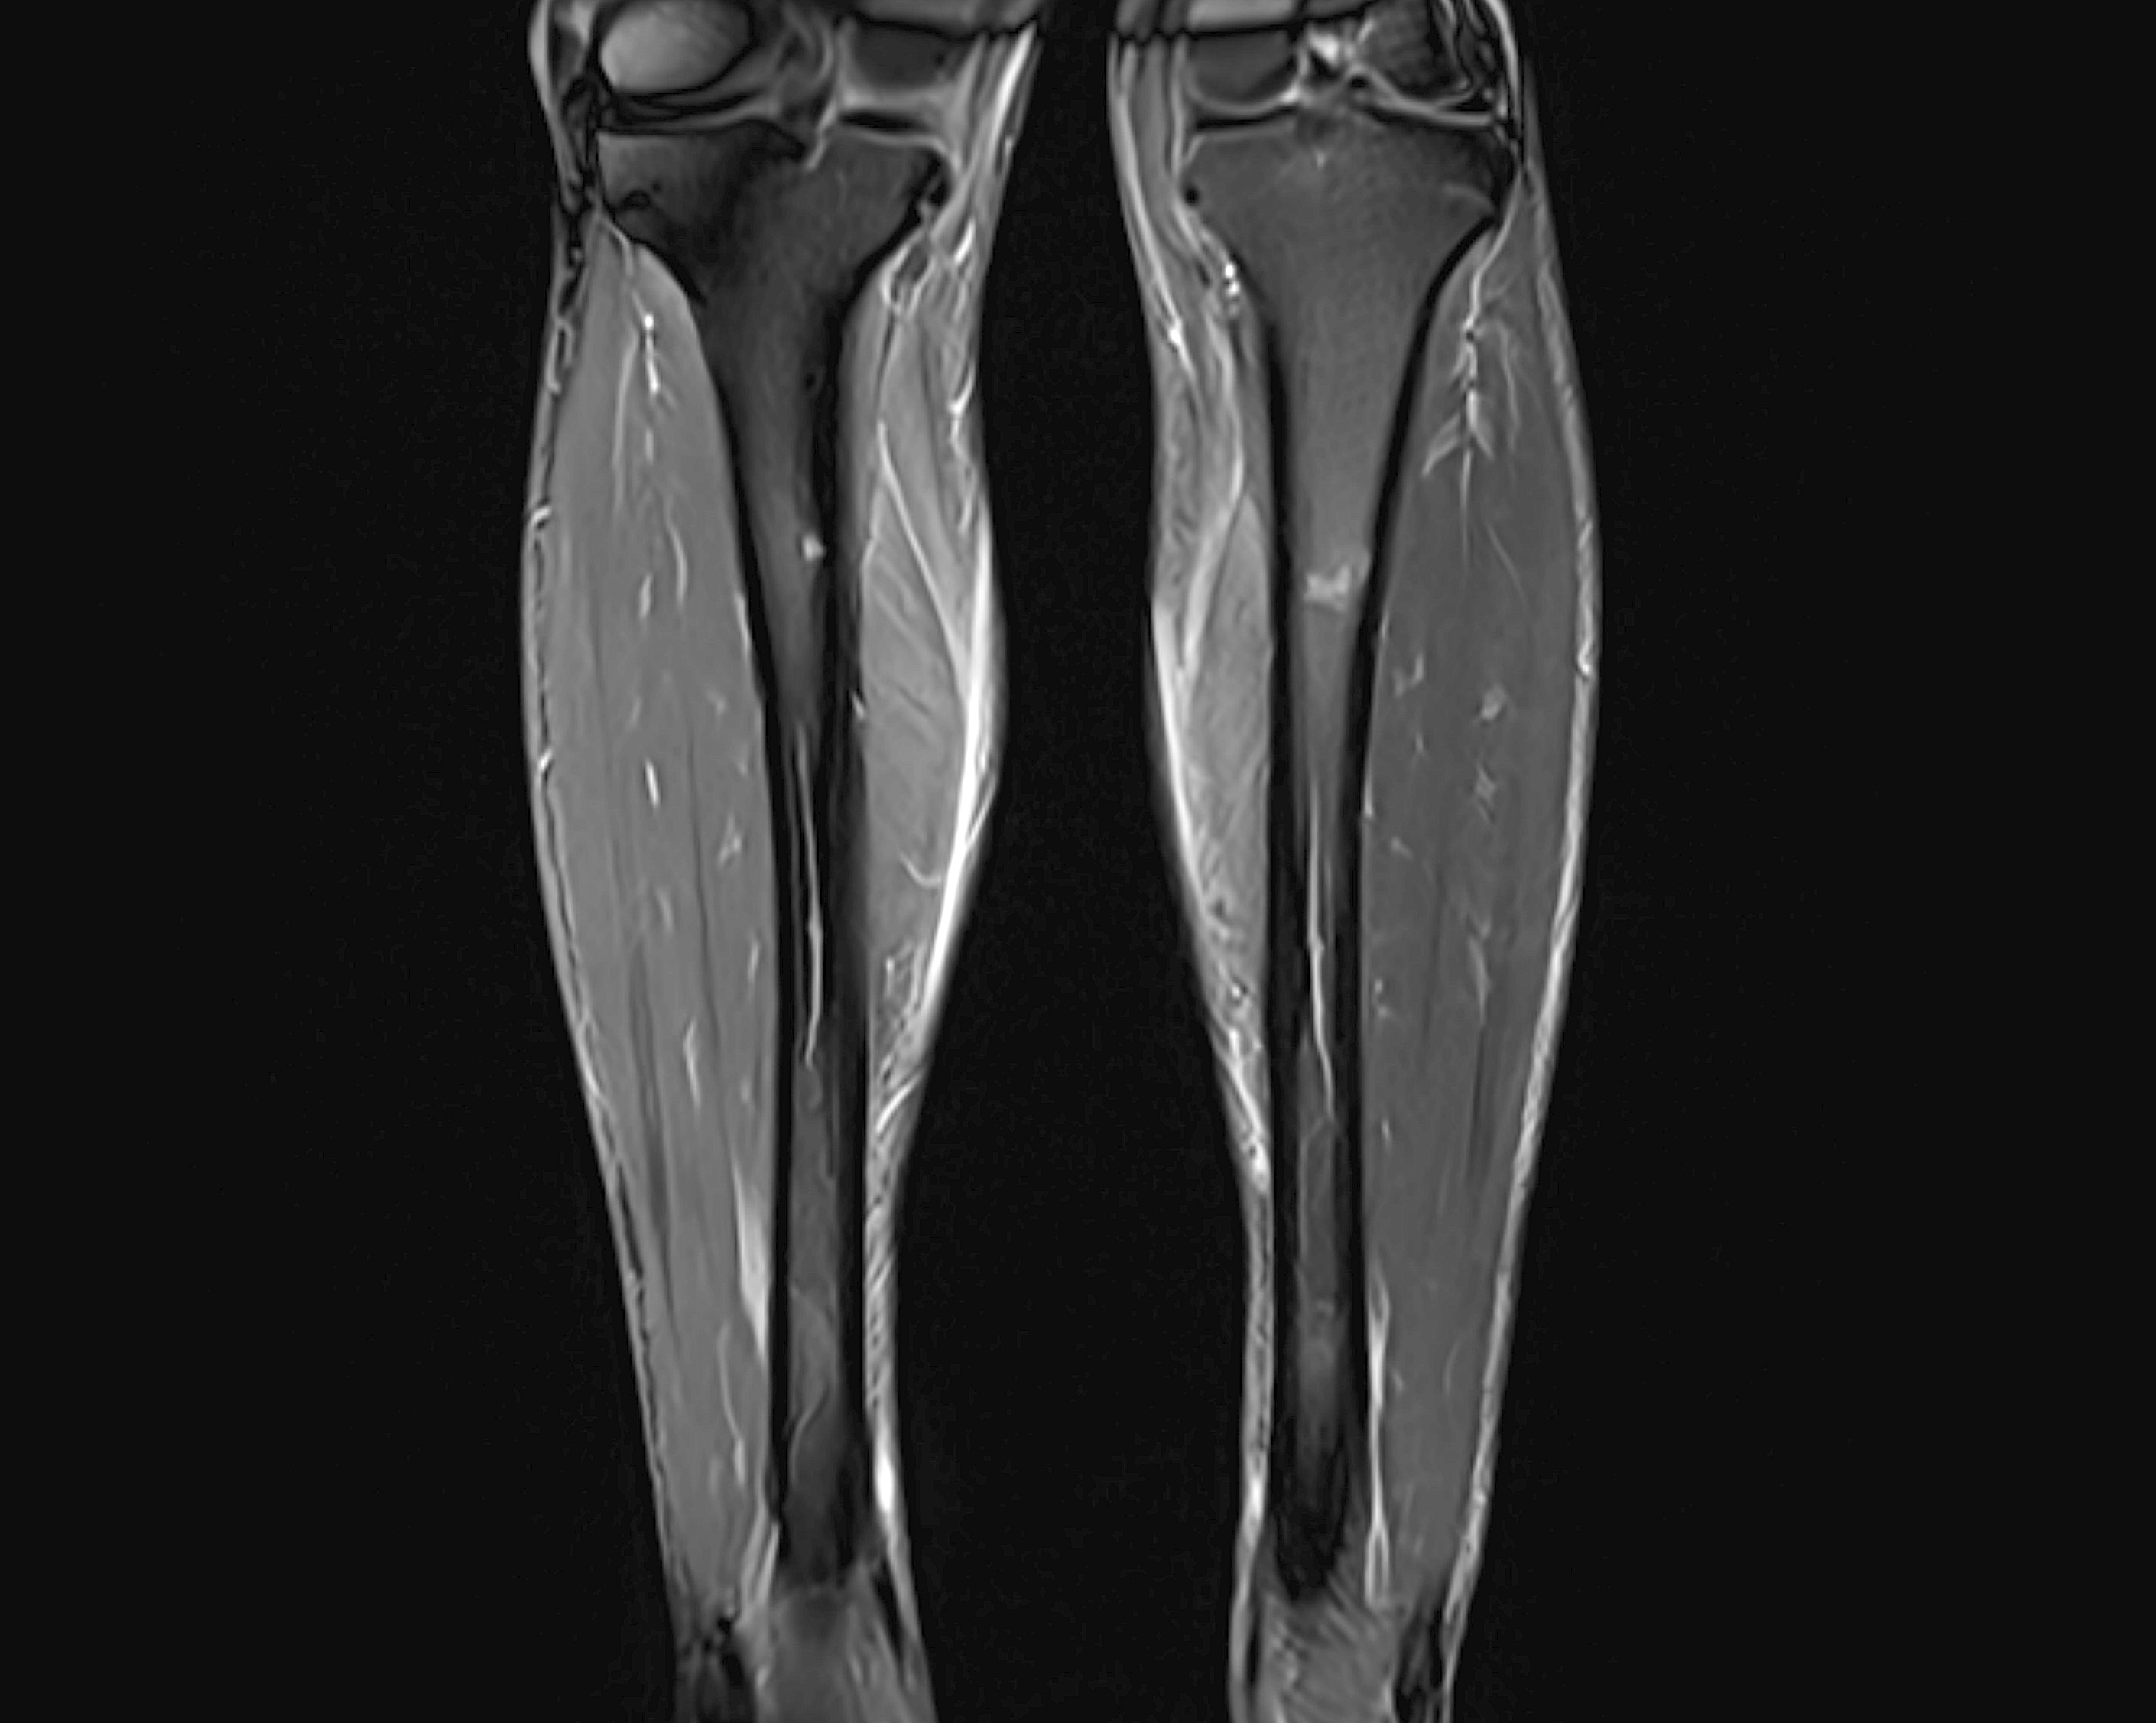

Vid en MR-undersökning av underbenet tas vanligtvis två projektioner – en i frontalplan (framifrån) och en i sidoplan (profil). Undersökningen ger en detaljerad insyn i benvävnad, senor, muskler, ledband och kärlstrukturer. Den är särskilt användbar för att utreda misstänkta frakturer, stressrelaterade sprickor, ledbands- eller senrupturer samt tidiga tecken på artros eller vävnadsslitage.

Undersökningen tar cirka 30 minuter och utförs i liggande position. Den är helt smärtfri, strålningsfri och ger högupplösta tvärsnittsbilder av underbenets olika strukturer – även vid svårbedömda fall där röntgen eller ultraljud inte ger tillräcklig information. MR undersöknignen är särskilt värdefull när röntgen inte kunnat förklara symtomen, eller när skadan sitter djupt i vävnaden.